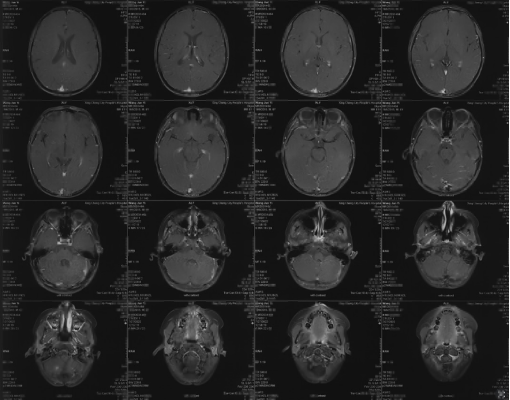

1-year postoperative imaging and follow-up

Postoperative enhanced MRI

Postoperative follow-up 1 year enhanced MR